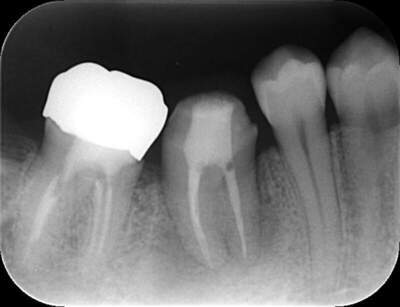

初診時のパノラマレントゲン

説明:

初診時のパノラマレントゲンです。右上の歯が虫歯によって大きく欠けているのがわかります。

移植した歯のレントゲン写真

移植した歯の写真です。隣の歯とワイヤーで固定します。約3週間でワイヤーは外します。

3週間後

3週間後のレントゲン写真

移植後3週間経ったら根管治療を行います。根管治療後はレントゲン撮影をし、お薬がしっかり根の先まで充填できているか確認します。この後、土台をたてて、かぶせ物をかぶせて治療終了です。